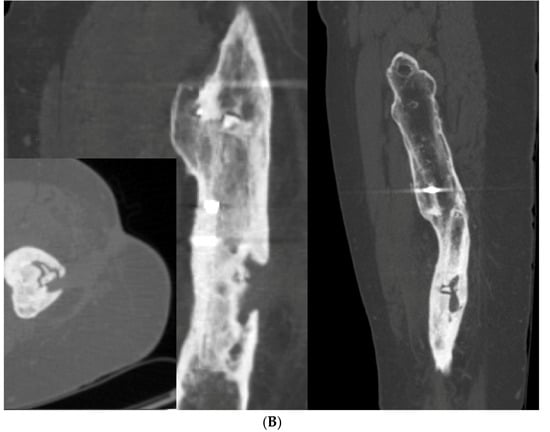

Figure 7.

(A) A young adult college baseball player sustained a closed tibia fracture with intact fibula, treated closed. The patient developed a recurvatum deformity with pain at the proximal and distal tibiofibular joints. (B) The patient demonstrated mechanical axis lateralization due to coronal plane translation with slight varus. The plane of deformity was calculated as 73 degrees off of the coronal plane. (C) The patient underwent focal dome osteotomy at the CORA (yellow circle) in the plane of maximum deformity. (D) Dual plate compression was used. Angulation and translation were simultaneously corrected. (E) Final follow-up 9 months: anteroposterior, lateral, and oblique films show the osteotomy healed. Tibiofibular joint pain resolved after osteotomy. Patient returned to college-level baseball.

A focal dome was chosen to correct the varus recurvatum and translation. The surgical approach was an anterior approach over the anterior compartment, elevating the tibialis anterior from the lateral tibia to allow safe access to the plane of the deformity. The fibula was osteotomized near the level of the tibia through a separate lateral approach. The plane of maximum deformity was assessed intraoperatively and confirmed the preoperative calculations. The ‘no deformity’ view on fluoroscopy was located, with the maximum plane orthogonal to this. It is in this plane that the drill bit at the CORA is directed, and this is especially important if correcting a translation. The arc of the osteotomy was drawn using a parallel drill guide with one bit centered at the CORA (Figure 7C).

The angulation and translation were simultaneously corrected. Dual medial–lateral plates were used to counteract the lateral gap forming with medial plate compression. Hence, balanced compression from the medial and lateral plates restored the alignment and provided absolute stability (Figure 7D). The patient had immediate relief of knee pain after correction. The soft tissue and osteotomy healed without incident (Figure 7E).